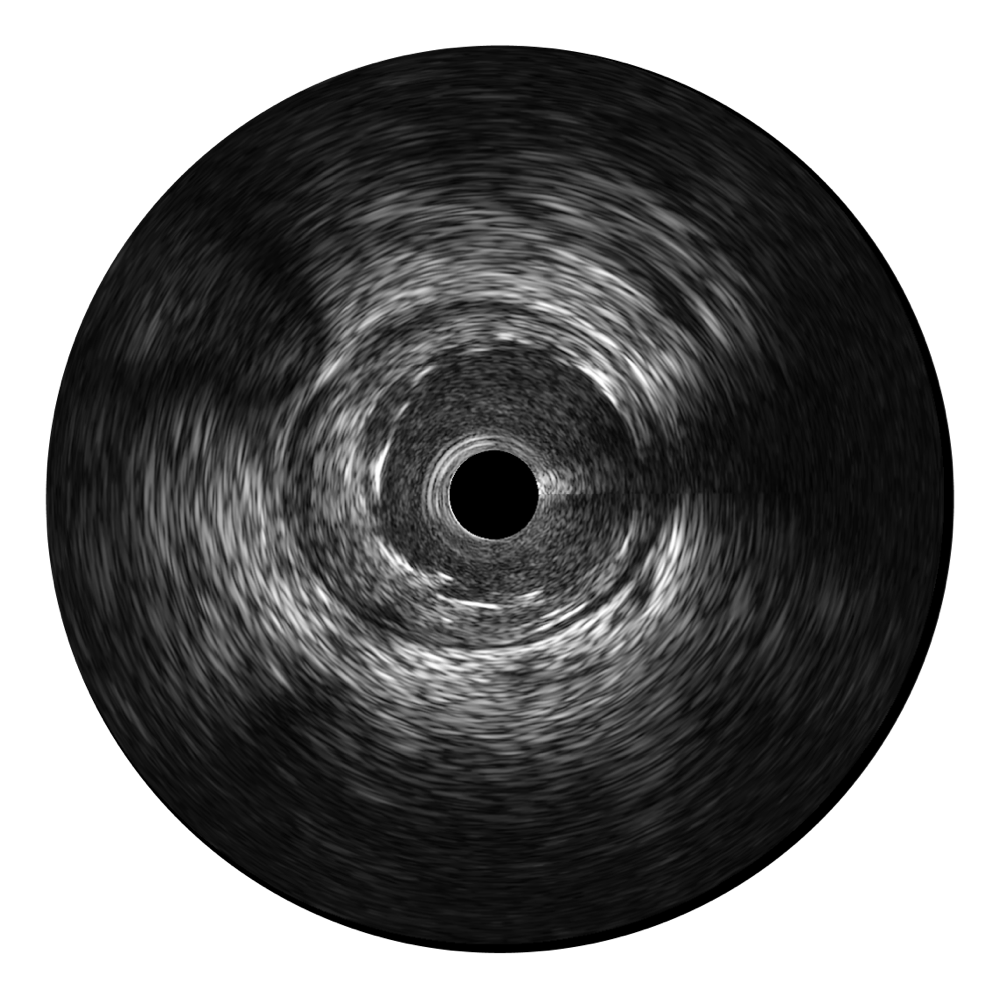

milan米兰超宽频成像技术覆盖20-80MHz1或20-90MHz2频率范围, 提供优异的分辨力同时也保证充足的穿透深度

对比传统IVUS导管成像,milan米兰宽频IVUS图像的近场支架梁显影更细腻,远场中膜外血管仍清晰可辨,兼顾远中近,兼顾分辨力与穿透深度